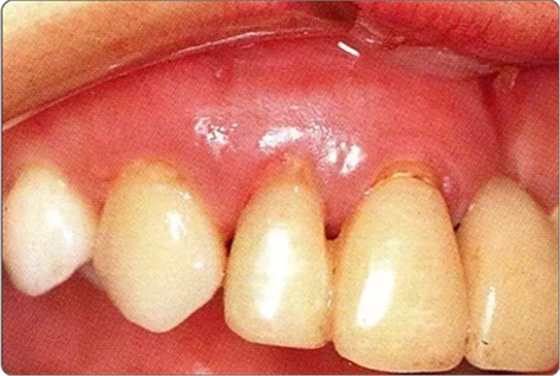

圖10-8 上頜腭側(cè)處縫合的狀態(tài)。為獲得一次性創(chuàng)傷治愈進行了緊密縫合

圖10-9 術(shù)后2周的狀態(tài)。牙齦乳頭獲得保存。較之使用GTR膜,自體骨移植更不容易引起牙齦乳頭的壞死。